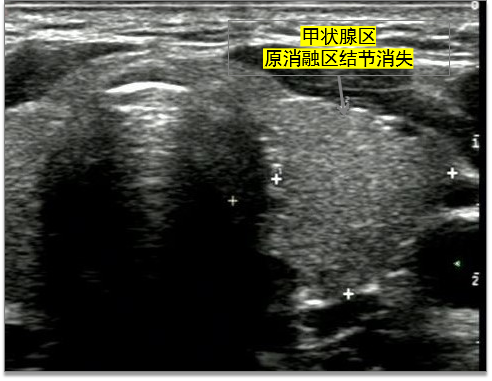

▲术后1年,超声检查中发现,消融灶消失。王女士对本次治疗效果表示满意。